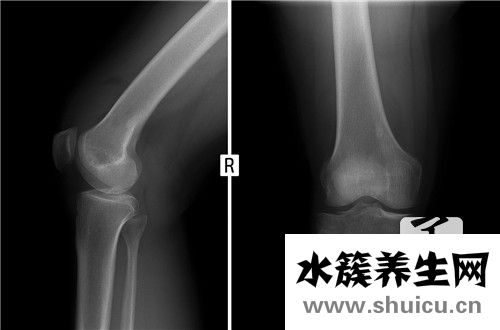

腓骨是只身中最多的兩個骨頭,腓骨的遠端是指我們腳踝的con突。 該位置是最小的區(qū)域,并且在受到外力的條件下可能會出現(xiàn)斷裂問題。 這個地方有骨折,立即影響了我們通常的步行活動,并且如果治療不正確,可能會導致修復不完全并引起一系列并發(fā)癥。

脛腓骨遠側骨折歸屬于踝關節(jié)骨折范疇,骨折端挪動大的需要手術醫(yī)治,假如醫(yī)治恰當,中后期基本沒有并發(fā)癥,你是石膏固定,需要固定不動6周不可以下床行走。

建議建議:建議每2周復診患側X光片看骨折恢復狀況及有沒有挪動,脛腓骨骨折成年人一般要4-6月痊愈,除去熟石膏后仍不可以負重,積極主動鍛練膝關節(jié)活動能降低并發(fā)癥,骨折普遍并發(fā)癥有外傷性關節(jié)炎

腓骨perone系下肢小腿肚長骨之一。偏細,在小腿肚兩側。上方彭大稱腓骨小頭,其中上邊有關節(jié)面與踝關節(jié)的腓關節(jié)面相連骨節(jié)。下方較彭大稱外踝,其中側邊有平整的外膝關節(jié)面,參加組成膝關節(jié)。此骨長細,起輔助、適用功效。此骨損害較多見,單純性腓骨骨折對下肢負重影響較小,但脛腓骨間神經、血管較多,易另外受損,故解決仍應十分注意。